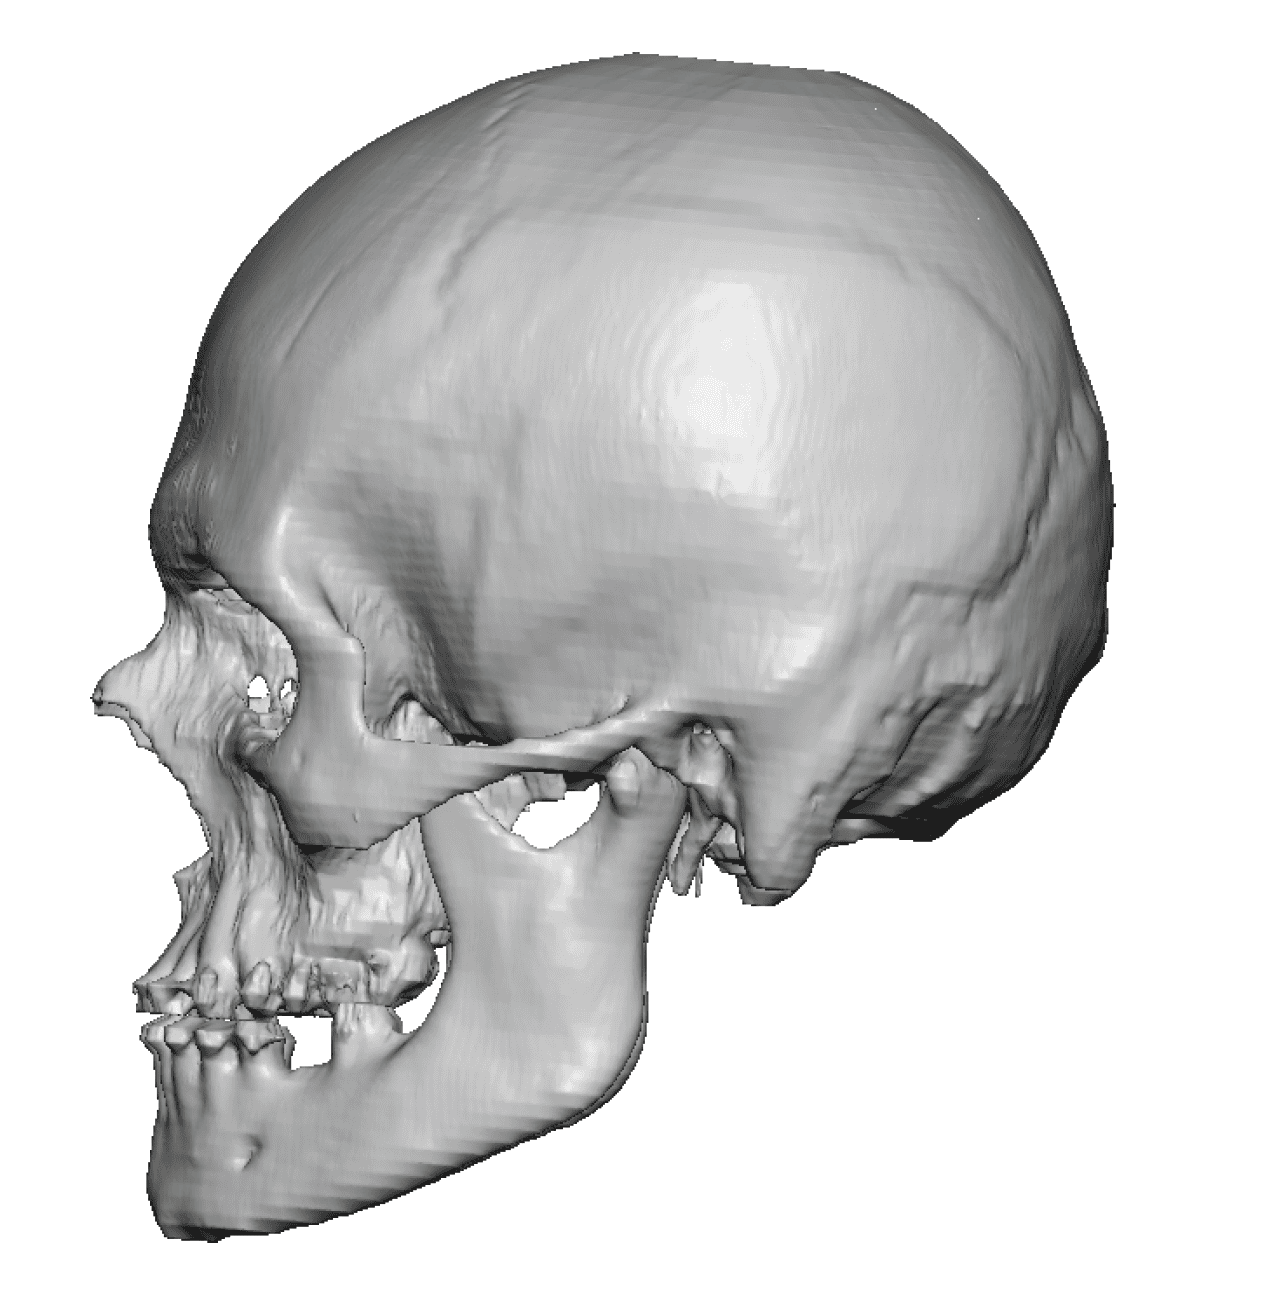

Patient 49

Desire for further skull augmentation after a primary skull implant.

Five years after an initial custom skull implant placement a new custom skull implant that increased the volume by 35% was placed.

Desire for further skull augmentation after a primary skull implant.

Five years after an initial custom skull implant placement a new custom skull implant that increased the volume by 35% was placed.